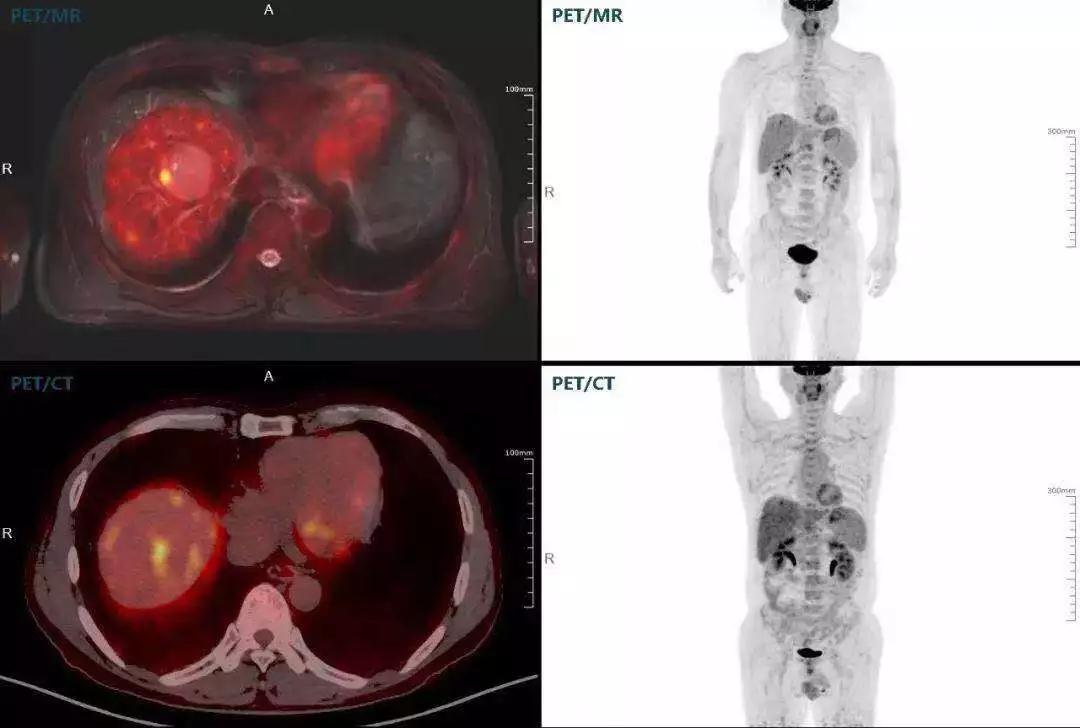

聯(lián)影“時(shí)空一體”超清TOF PET/MR搭載的壓縮感知技術(shù),能夠同時(shí)實(shí)現(xiàn)16期成像,精準(zhǔn)捕獲肝臟動(dòng)態(tài)影像的每一瞬間,同時(shí)兼顧早期與晚期等全部期相的完整病灶信息,實(shí)時(shí)、全方位鎖定病灶。同時(shí),基于其2.8mm超高分辨率,能夠精細(xì)呈現(xiàn)腫瘤邊界信息,捕捉局部微小病灶與遠(yuǎn)端轉(zhuǎn)移灶,助力醫(yī)生精準(zhǔn)診斷。

(對(duì)于同一例肝臟惡性腫瘤,PET-CT與PET/MR成像對(duì)比。可以看到,聯(lián)影PET/MR圖像對(duì)腫瘤邊界和FDG高濃聚區(qū)域清晰顯示。)